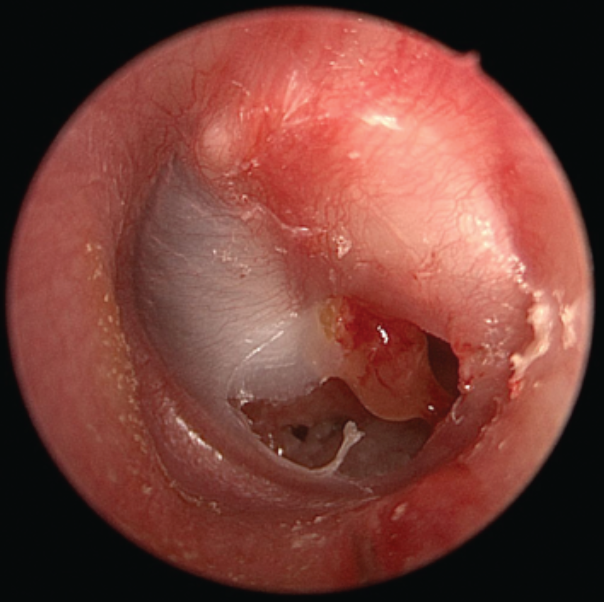

Chronic Suppurative Otitis Media

Also known as chronic mucosal otitis media. Differs from AOM by duration (>6 weeks)

Chronic Squamous Otitis Media secondary to cholesteatoma

Warning

Patients with an attic perforation (squamous chronic otitis media) or persistent crusting or granulation (above the malleus, in the top part of the TM) should be referred to an ENT surgeon immediately to exclude cholesteatoma